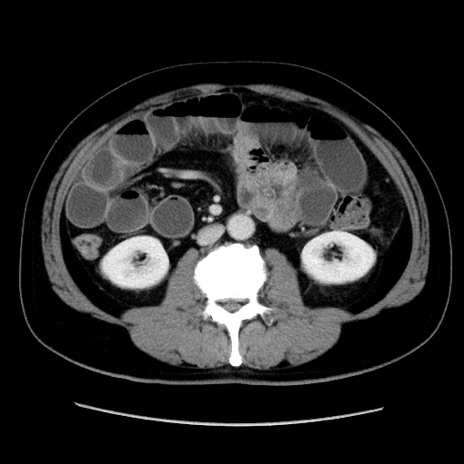

症例16(横断像)

【症例】 70歳代男性

【主訴】 腹痛、嘔吐

【現病歴】 約1ヶ月前より間欠的に腹痛と嘔吐あり、当院消化器内科を受診したところCTで多発する肝臓のLDAを指摘され、精査中であった。以降は消化器症状は安定していたが、2日前より嘔気と腹痛があり、同日より排便・排ガスが消失した。改善認めず、 本日、救急外来を受診した。

【身体所見】意識清明・会話良好、BT 36.3℃、BP 127/80mmHg、 P 80bpm、腹部:膨満あり、平坦・軟、上腹部正中および下腹部正中に圧痛あり、反跳痛なし、筋性防御なし。

【データ】WBC 7200、CRP 0.77